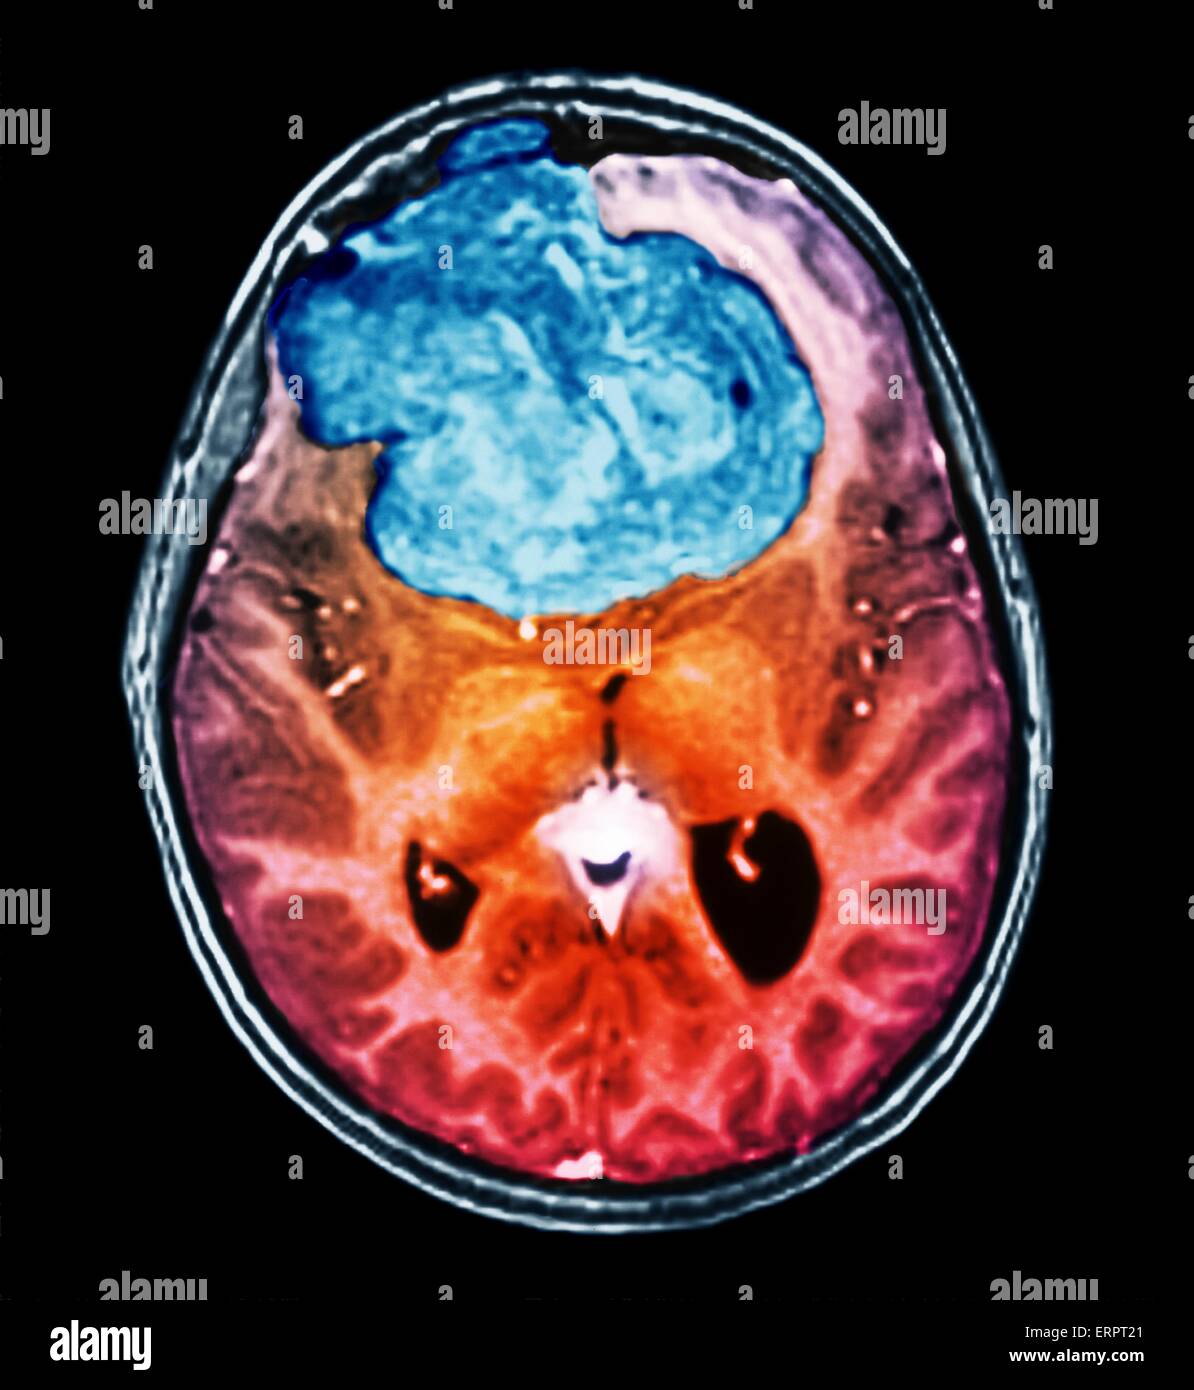

Tumeur bénigne au cerveau. La tomodensitométrie (CT de couleur) du cerveau d'un patient de 25 ans avec un méningiome (bleu). Il s'agit d'une bénigne (non cancéreuse) tumeur qui découle de la méninges, les membranes qui entourent le cerveau. Il a été causé par radi Banque D'Imageshttps://www.alamyimages.fr/image-license-details/?v=1https://www.alamyimages.fr/photo-image-tumeur-benigne-au-cerveau-la-tomodensitometrie-ct-de-couleur-du-cerveau-d-un-patient-de-25-ans-avec-un-meningiome-bleu-il-s-agit-d-une-benigne-non-cancereuse-tumeur-qui-decoule-de-la-meninges-les-membranes-qui-entourent-le-cerveau-il-a-ete-cause-par-radi-83480377.html

Tumeur bénigne au cerveau. La tomodensitométrie (CT de couleur) du cerveau d'un patient de 25 ans avec un méningiome (bleu). Il s'agit d'une bénigne (non cancéreuse) tumeur qui découle de la méninges, les membranes qui entourent le cerveau. Il a été causé par radi Banque D'Imageshttps://www.alamyimages.fr/image-license-details/?v=1https://www.alamyimages.fr/photo-image-tumeur-benigne-au-cerveau-la-tomodensitometrie-ct-de-couleur-du-cerveau-d-un-patient-de-25-ans-avec-un-meningiome-bleu-il-s-agit-d-une-benigne-non-cancereuse-tumeur-qui-decoule-de-la-meninges-les-membranes-qui-entourent-le-cerveau-il-a-ete-cause-par-radi-83480377.htmlRFERPT21–Tumeur bénigne au cerveau. La tomodensitométrie (CT de couleur) du cerveau d'un patient de 25 ans avec un méningiome (bleu). Il s'agit d'une bénigne (non cancéreuse) tumeur qui découle de la méninges, les membranes qui entourent le cerveau. Il a été causé par radi